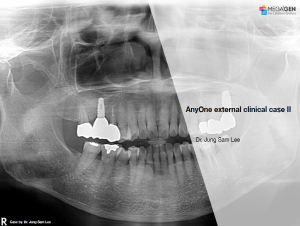

Miguel Stanley, Filipa Calheiros Braga, and Beatriz Mota Jordao, AnyRidge, Immediate Loading, Anterior Maxilla, Scientific background, single replacement